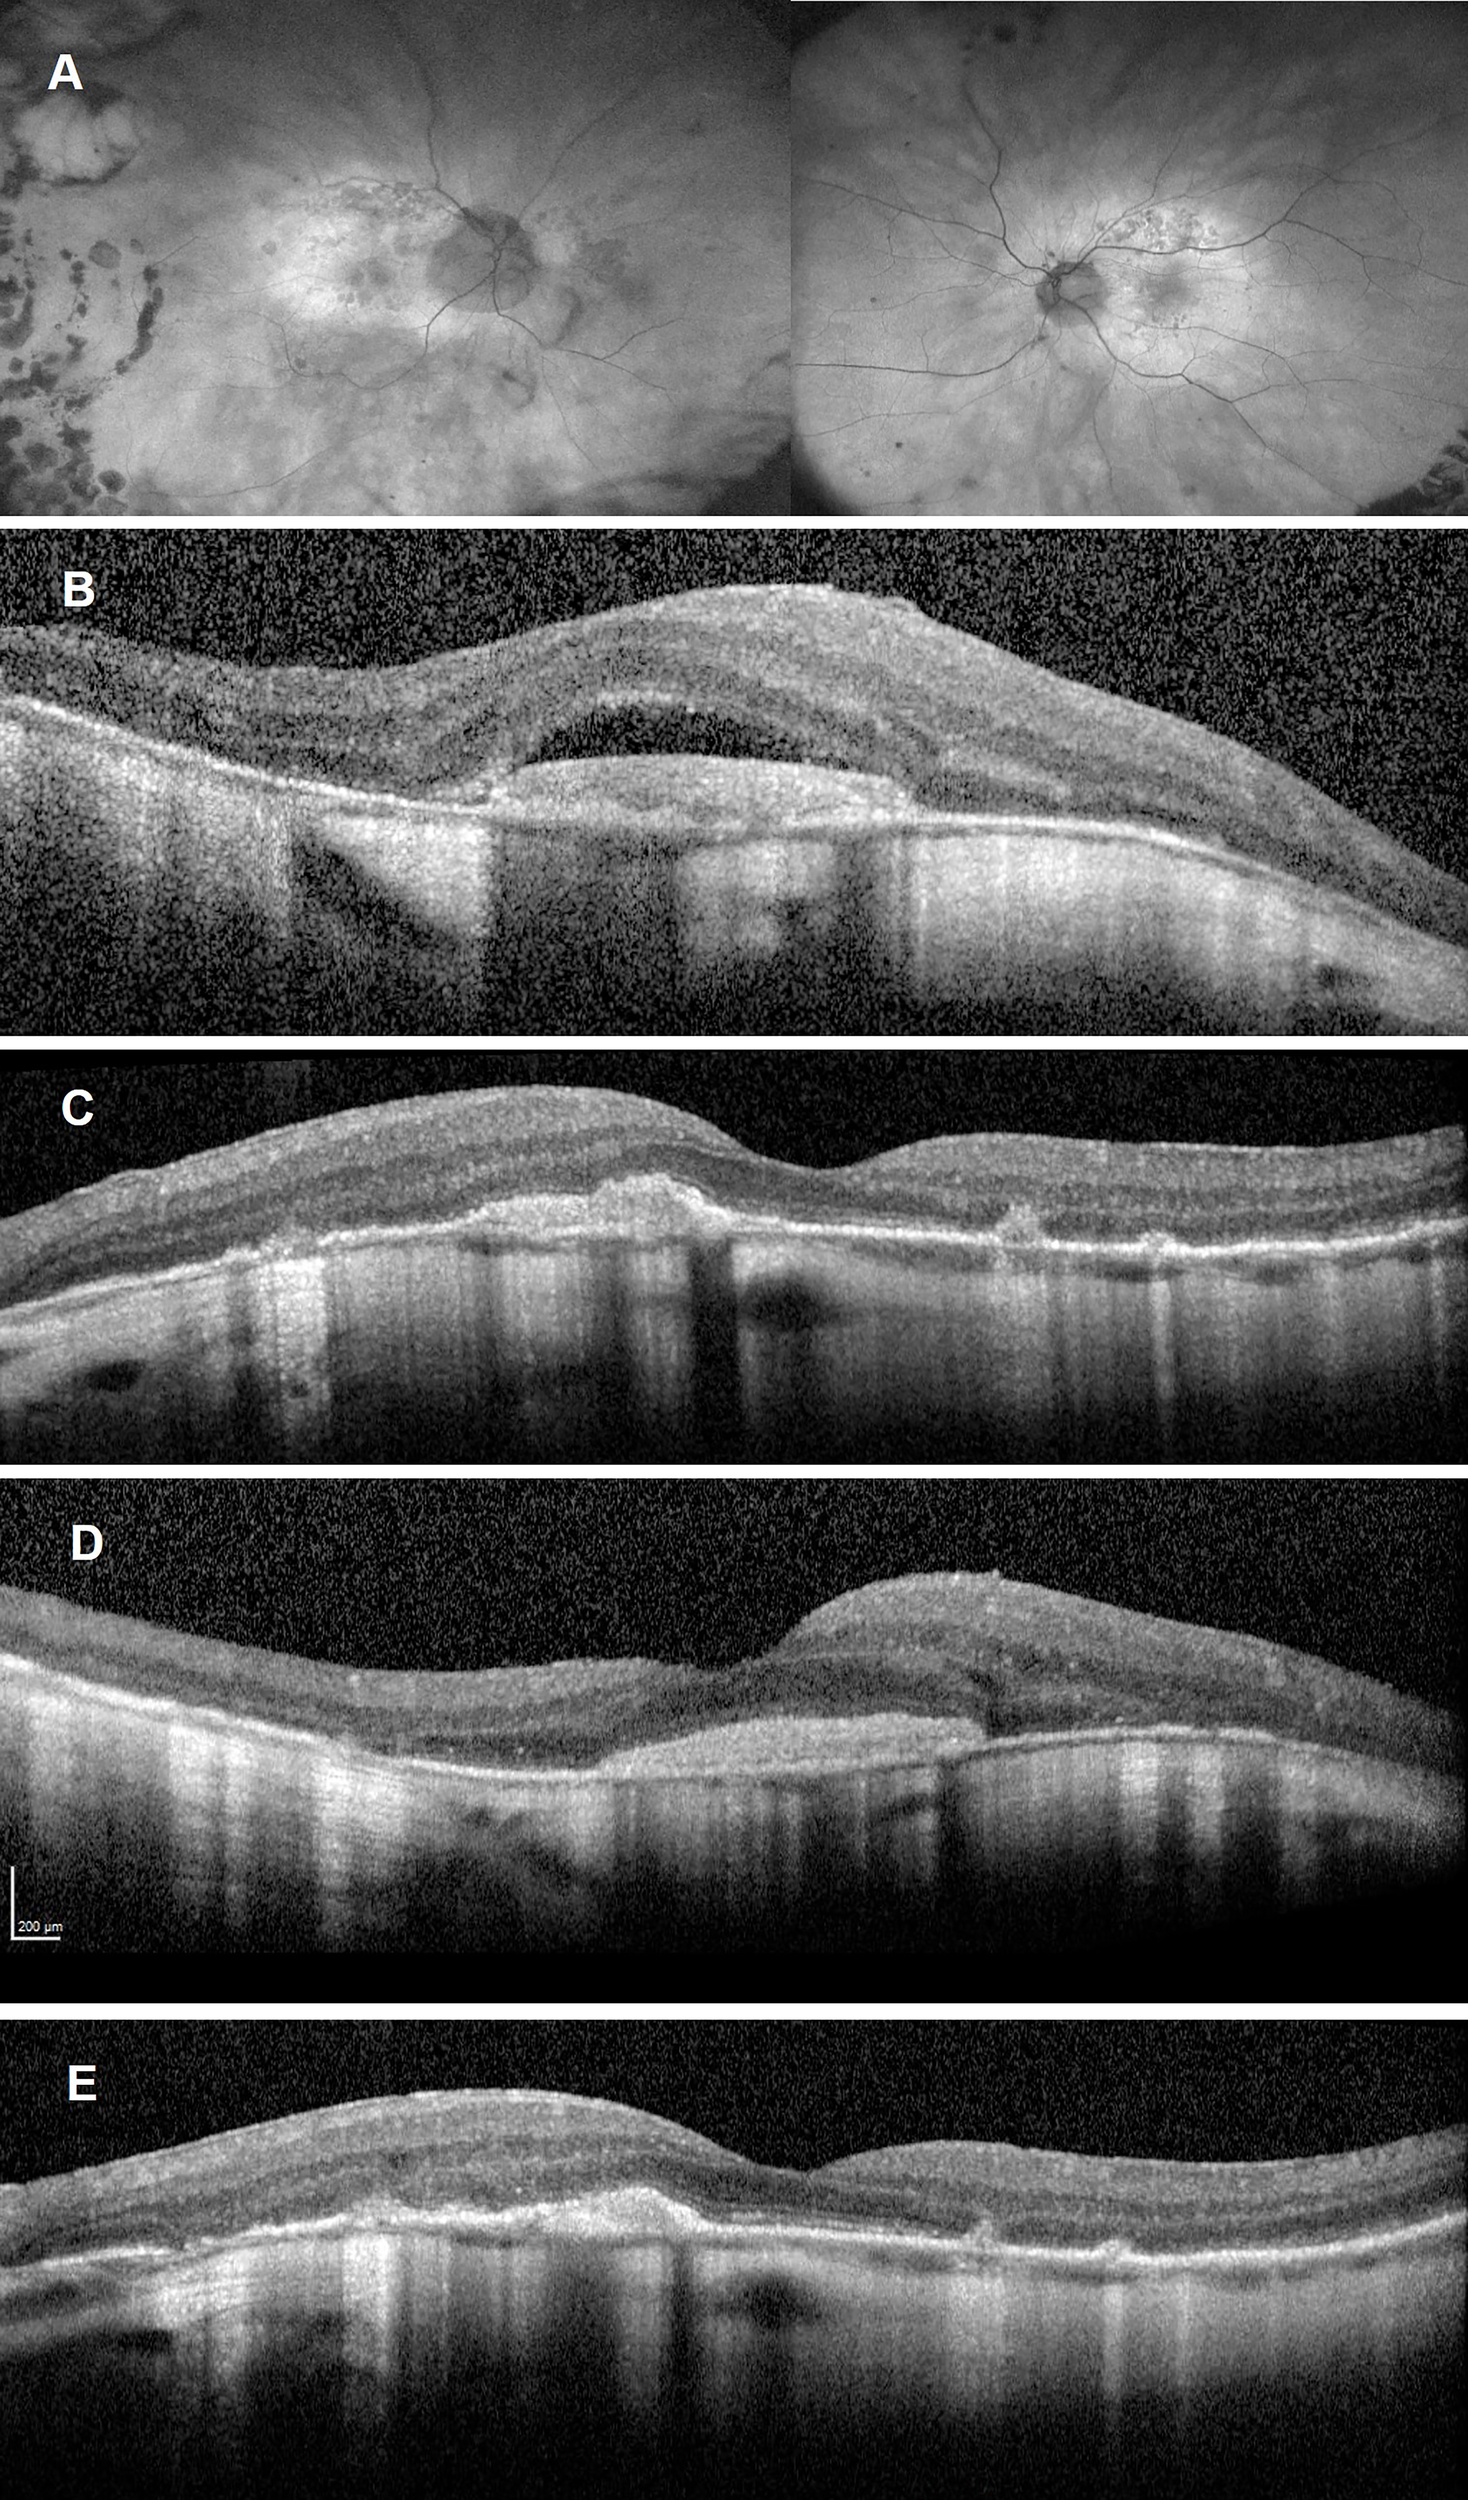

Following two intravitreal aflibercept injections, BCVA improved to 6/12 OD and 6/6 OS. FAF demonstrated fading of the hyperautofluorescent placoid lesions in the posterior poles (Figure 3A). SD-OCTs showed a gradual resolution of SRF in the both eye (Figures 3B–E), indicating good clinical and anatomical response to aflibercept monotherapy. Syphilis serology following anti-treponemal treatment has not yet been repeated.

Figure 3

Follow-up imaging after commencement of aflibercept treatment and completion of anti-treponemal therapy. Ultra-widefield autofluorescence of both eyes (A) showing fading of the hyperreflective placoid lesion and progressing multifocal retinal pigment epithelium atrophy. Spectral Domain-Optical Coherence Tomography (SD-OCT) after one aflibercept injection showing persistent subretinal fluid overlying a disciform scar in the right eye (B) and resolution of subretinal fluid but persistent subretinal hyperreflective material left eye (C). SD-OCT after two aflibercept injections showing a significant reduction in subretinal fluid over a largely unchanged disciform scar in the right eye (D) and a reduction in the subretinal hyperreflective material as well as reconstitution of the inner segment ellipsoid zone in the fovea of the left eye (E).